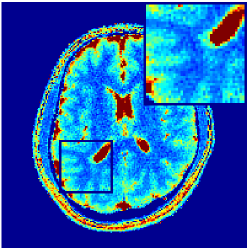

Two sets of experiments were conducted here: first, we used the 2D and 3D acquisition sequences for scanning a healthy volunteer’s brain (real-world acquisitions). Figures 6 and 7 display the parametric maps reconstructed from 2D spiral and radial readouts. We computed the T1, T2 and proton density (PD) maps using baseline reconstruction algorithms ZF, VS, LR, FLOR, AIR-MRF and our proposed LRTV. While baselines use DM either for quantitative inference or also during reconstruction (i.e. AIR-MRF), we further compare the DM-free LRTV’s performance when cascaded to DM, KM and MRFResnet for quantitative inference. For the 3D spiral acquisitions we compared LRTV and its closest competitor VS in Figure 8. Outcomes from other tested algorithm are displayed in the supplementary materials (Figure S5). Since FLOR does not use dimensionality-reduction, our system ran out of memory during 3D reconstruction; hence results are not reported in this case.

VI-E1 Discussion

The LRTV-DM and LRTV-MRFResnet perform on par, and both outperform all tested baselines for reconstructing T1, T2 and PD maps in all acquisition schemes. This can be observed both visually in Figures 6, 7, 8, S2 and S3, and quantitatively in Table IV across all tested metrics. Other baselines were unable to successfully remove the under-sampling artefacts in TSMIs, and these errors propagated to the parameter inference phase and resulted in inaccurate maps. Temporal-only priors incorporated within LR are shown insufficient to regularise the inverse problem and LR sometimes (e.g. 2D spiral acquisitions) can admit solutions with even stronger artefacts than the model-free ZF baseline. This issue was previously studied for other non-Cartesian MRF readouts that similar to our spiral/radial trajectories, miss to sample the corners of the k-space in all timeframes (see section 2.2.2 and figure 2 in [19]). In the absence of reference for the k-space corners information, the LR iterations despite minimising the objective can converge to solutions with high-frequency artefacts, as visible in the computed maps. This highlights the need for adding an appropriate spatial-domain regularisation. FLOR reduces the LR’s artefacts but this improvement is limited because the suggested nuclear norm penalty does not incorporate an explicit spatial regularisation. Further for reducing artefacts, FLOR can introduce an undesirable bias in the computed T1/T2 maps e.g. see error maps in Figures S2 and S3. The non model-based VS baseline incorporates spatial regularisation and results in spatially smoother maps than ZF and LR, but it is unable to output artefact-free images. Further and consistent with our in-vitro experiment, we observe that VS overestimates the T2 values (e.g. in White and Grey matter regions) in tested 2D acquisitions i.e. the spatial regularisation trades off agains the quantification accuracy. The model-based AIR-MRF adds spatial regularisation through 2D/3D low-pass Gaussian filters however this trades off the sharpness of the computed maps and can increase the errors at the tissue boundaries (we searched Gaussian spreads that keep the blurs and high-frequency artefacts minimal). For our acquisition readouts, Gaussian filters performed better than disk filters of [19] for avoiding strong Gibbs artefacts. On the other hand, the spatiotemporally regularised LRTV greatly improves the TSMI reconstructions i.e. 4 dB enhancement compared to the closest competitor baseline (Table IV). This enables computing accurate and aliased-free multi-parametric inference using DM or the DM-free learning-based alternative MRFResnet as visible in Figures 6, 7, 8, S2 and S3. MRResnet and DM score competitive quantitative inference results i.e. T1 and T2 MAPE less than 5% and 9%, respectively (Table IV). KM also outputs comparably accurate T1 maps, however this shallow learning model despite having a model size larger than MRFResnet, is unable to learn accurate T2/PD quantification and it results in poor estimated maps, consistent with our observations in section VI-C.